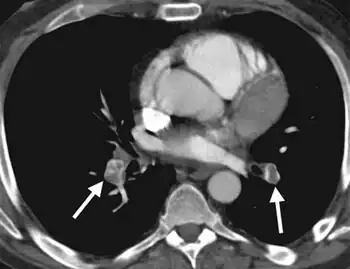

| CT-pulmo-angiographic exam, bilateral massive pulmonary embolism was confirmed | |